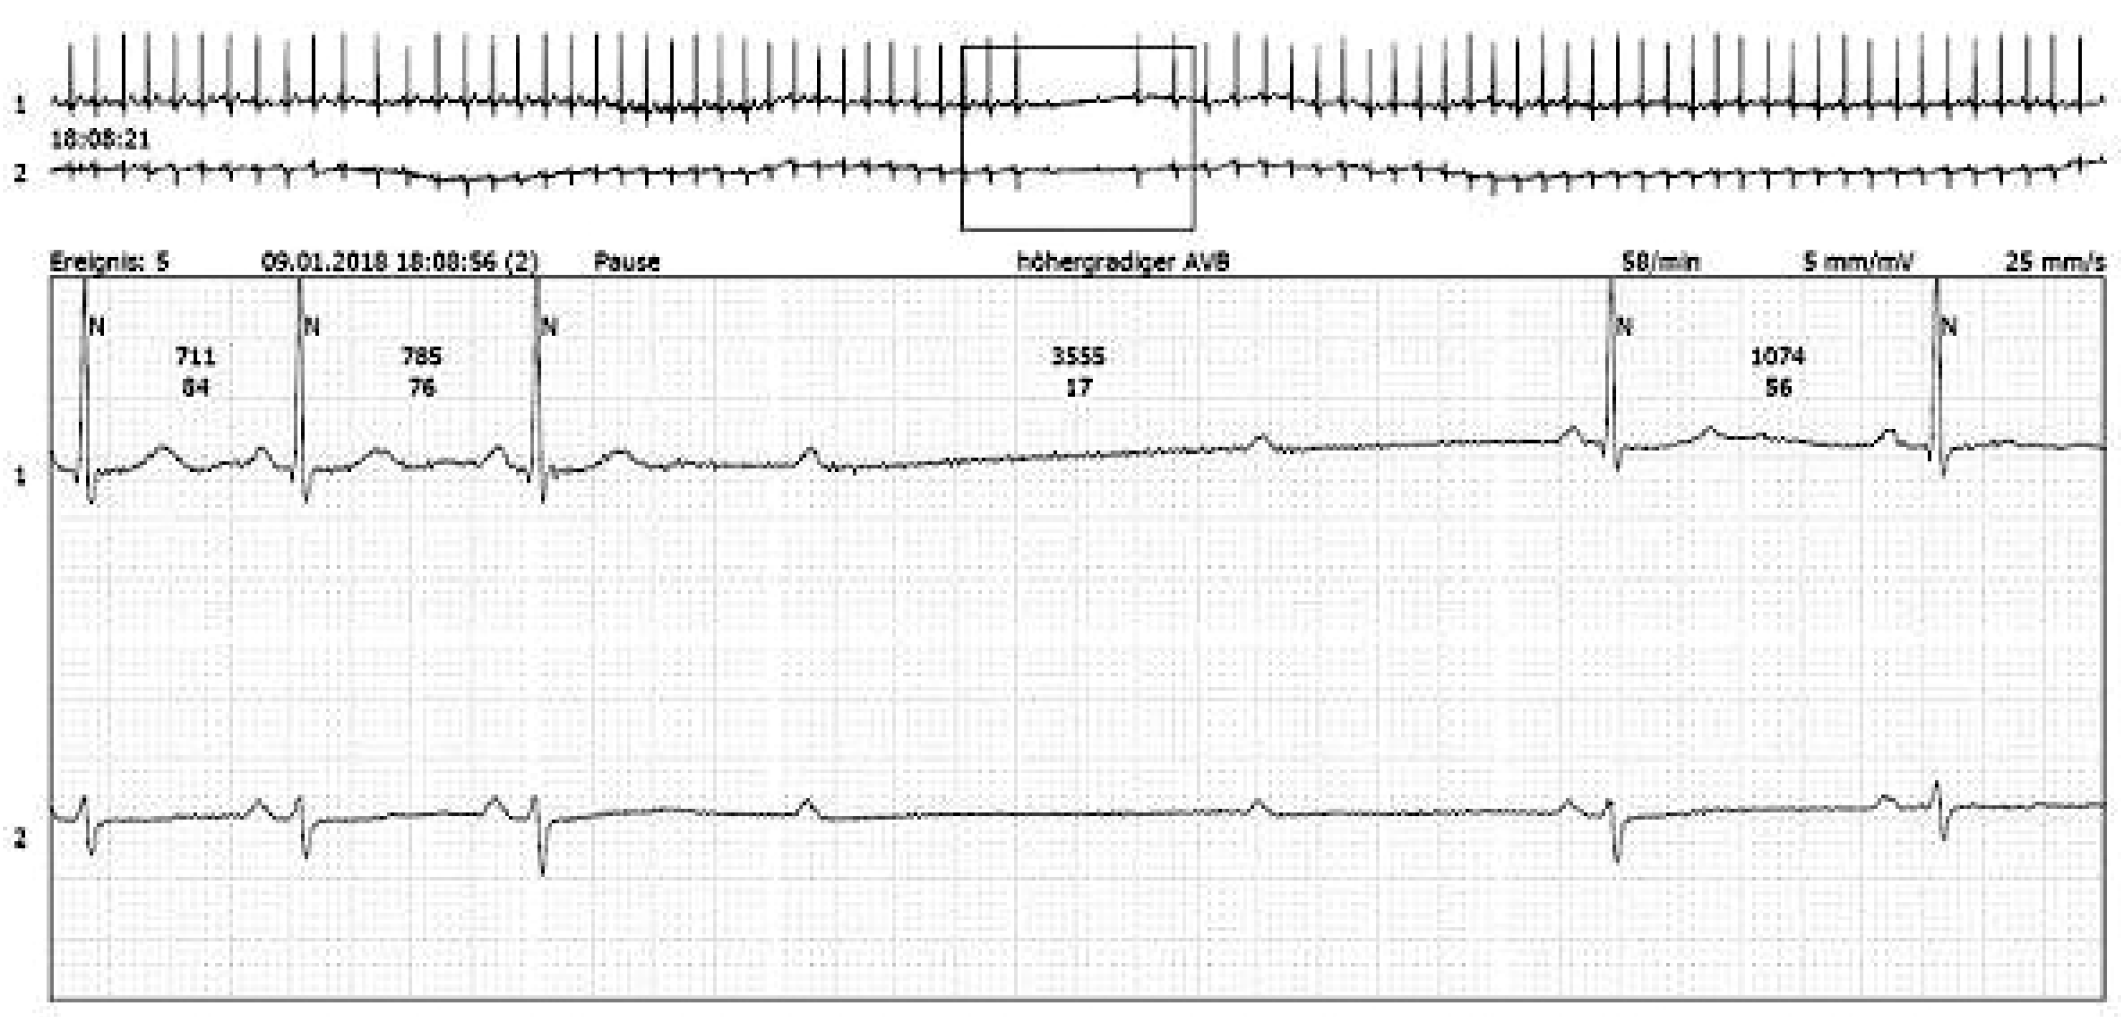

Background: Two mechanisms may explain the occurrence of Torsades de Pointes tachycardia (TdP) in atrioventricular block (AVB): (1) a phase 2 reentry phenomenon in adjacent myocardial fibers due to bradycardia and (2) a fast reentry circus movement. Therefore, the objective of this study was to investigate mechanisms of TdP, and to present for the first-time endocardial recordings during TdP from patients with high-degree AVB.

Methods: TdP was recorded by surface ECG in 16 patients with high-degree AVB. The critical coupling interval (CCI) between the last beat during AVB and before the first abnormal ventricular event (PVCs, couplets, triplets and TdPs) was measured. Endocardial signals during TdP were recorded from the right ventricular apex by temporary bipolar catheters.

Results: Patients were >65 years; 80% were females. The QT interval during AVB (mean heart rate of 38.9 ± 7.5 bpm) was 653 ± 67.2 ms. The CCI before the onset of PVCs/couplets vs. TdP was shorter in the latter (672 ± 43.8 ms and 676 ± 37 ms vs. 639 ± 52 ms, p <0.05). A rhythmic crescendo (in 100%) of PVCs and T wave augmentation (in 75%) was observed before the onset of TdP (figure, A, arrow). In 4/5 patients (75%) the local endocardial electrogram showed a constant pattern of rapid deflection superimposed on a smooth low amplitude signal suggesting far field potentials from electrically depressed myocardium, indicating a phase 2 reentry (figure, B, arrow).

Conclusions: This study suggests abnormal repolarization of adjacent ventricular myocardial fibers indicating a phase 2 reentry and fast reentry circus movement as the cause of TdP in patients with high degree AVB.

![]() |

| Figure |